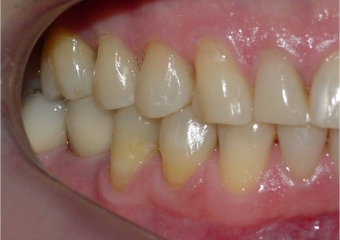

Mordida, após 2 anos da cirurgia